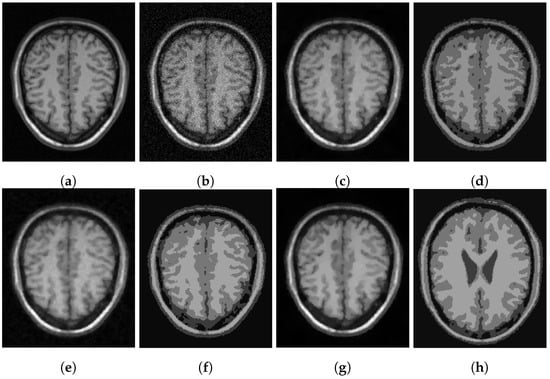

In Figure 3, Figure 4 and Figure 5, we show some examples of multiphase segmentation on MRI images of the brain. In all cases, we add Gaussian noise with mean 0 and standard deviation 17 and run the noisy image as input to both for all models but the CRCV model (as this is a two-phase model only). The output is then given as input to the k-means algorithm with . We show the clustering output in the final column of the relevant figures. We see that the segmentation result of our model is better at finding some of the finer edges; for example, the white matter segmentation from our model is in general more detailed than the segmentation from the competing ones.

Figure 4.

MRI segmentation: (a) Clean image. (b) Noisy image used as input to the models. (c) Output of CCZ. (d) CCZ after thresholding. (e) Output of CNC. (f) CNC after thresholding. (g) Output of T-ROF. (h) T-ROF after thresholding. (i) Output g of our model. (j) Output of our model. (k) Output of our model. (l) Ours after thresholding.